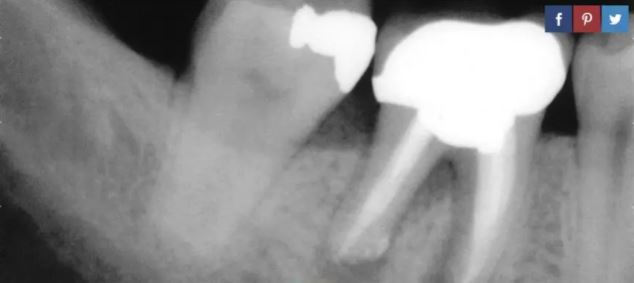

每年全世界的牙醫們要用鑽出「壞牙」、加入填充物的方法處理數億個牙洞。但根據資料,這種療法的失敗率在15% 以上,這就導致患者們需要進行根管治療來去除牙髓。所謂牙髓,就是牙體中心的軟組織,其包含血管、神經及結締組織。這種療法的缺點是,在完成根管治療後,牙齒強度會降低,最終病人不得不選擇拔牙。

治療性生物材料研究人員亞當·塞利斯(Adam Celiz)相信幹細胞有助於減少病人進行根管治療的次數,並降低他們對假牙的需求。塞利斯和他的團隊開發了一種由幹細胞製成的新型填充物,這種填充物能促進牙齒癒合。同常規填充物一樣,這種新型填充物也需要將生物材料幹細胞注入牙齒並用紫外線進行硬化。

「現有的牙齒填充物都對細胞具有毒性,因此並不能與牙齒內的牙髓組織相容。在牙髓損傷、患病情況下,醫生通常採用根管治療除去感染組織。而我們設計的合成生物材料作用與牙齒填充物相當,並且可直接與牙髓組織接觸,從而刺激天然幹細胞群體,使之對牙髓組織和周圍牙本質進行修復和再生。我們的方法一定會對牙科領域產生深遠影響。獲得這個獎為我們進一步與工業夥伴合作,共同發展這一技術提供了良好的平台。」

塞利斯認為,所有的填充物都應該用這種再生材料製成。這樣受損的牙齒就可以自行癒合,理論上,也可以減少填充失敗使得患者完全不必接受根管治療。

研究人員認為,如果牙齒受損,這些幹細胞會對其進行修復。這種新材料的作用與填充物相同,但出現相斥或失敗的風險極低。簡單來說就是在幹細胞生物填料的幫助下,牙齒會自行癒合。